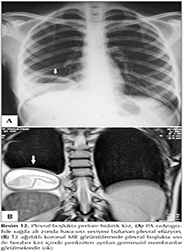

Subpulmoner Plevral Sıvı

Plevral sıvı bazen akciğerin alt y?zeyi ile diyafragma yaprağı arasında toplanmaktadır (Resim 4). Tek taraflı veya iki taraflı olabilir. Subpulmoner plevral sıvı olasılığını dışlamak i?in lateral dek?bit grafi ?ekilmelidir. Başlıca radyolojik bulgular;

Resim 4

a. Tek taraflı veya iki taraflı diyafragma kubbesinde y?kselme,

b. Diyafragmanın en y?ksek noktası, orta hatta olması gerekirken diyafragmanın 1/3 orta ve 2/3 lateral birleşimine yakın ve daha lateralde lokalizedir.

c. Diyafragma kubbesi lateral kostofrenik a?ıya doğru daha keskin eğim g?sterir,

d. Subpulmoner sıvı solda lokalize ise diyafragma ile mide hava cebi arasındaki mesafe 2 cm'den fazladır,

e. Lateral radyografide subpulmoner sıvı, alt lobun altında yatay ?izgi şeklinde g?r?l?r. Sıvıya ait bu ?izgi ?nde major fiss?r d?zeyinde dik olarak aşağıya iner,

f. Pulmoner vask?ler yapılar diyafragma konturunun arkasında izlenmesi gerekirken subpulmoner sıvının oluşturduğu yalancı kontur "ps?dodiyafragmatik kontur''un arkasında vask?ler yapılar g?r?lmez,

g. Kostofrenik sin?sler kapalıdır (4-6).